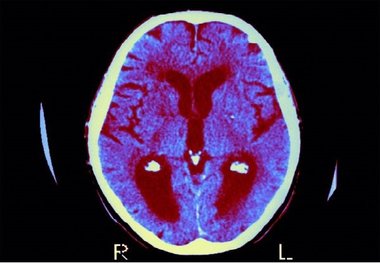

• فراموشی زودهنگام در کودکان؛ پای سرب در میان است

فراموشی زودهنگام در کودکان؛ پای سرب در میان است

بر اساس یک مطالعه جدید، قرار گرفتن در معرض سرب در دوران بارداری و اوایل کودکی ممکن است سرعت فراموشی اطلاعات در کودکان…